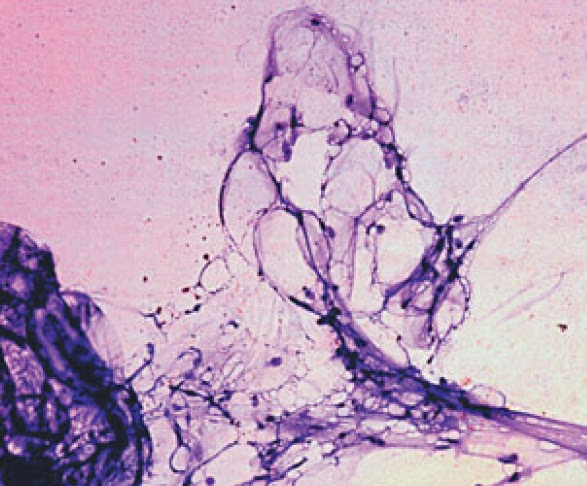

A 5-month old female cat presents to you for weight loss, chronic diarrhea and steatorrhea. The organism seen in a stained fecal smear is shown in the image below (this is a magnified 40X image, the organism is approximately 15 x 8 um). Which treatment is most appropriate

d) Fenbendazole

The organism is Giardia which can be recognized as a trophozoite with two nuclei outlined by adhesive discs. Giardia should be distinguishable from trichomonads which have a single nucleus and an undulating membrane.

The best treatments for Giardia are either fenbendazole or metronidazole.